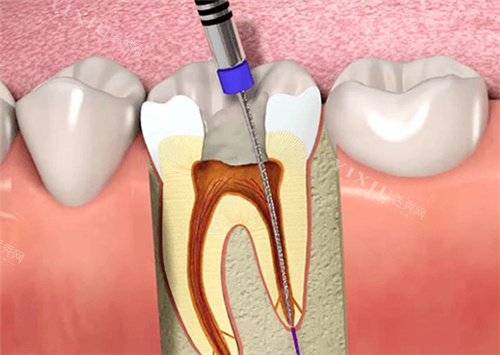

没等一会儿,护士就带我去了诊室。给我看牙的是张医生,他看起来特别和蔼,说话也轻声细语的。张医生先让我躺在牙椅上,然后仔细地检查了我的牙齿,还拍了片子。看着片子,他耐心地跟我说:“你这颗牙因为龋坏太严峻,已经伤到牙髓了,所以才会这么疼。不过别担心,咱们做根管治疗就能把问题解决掉。”接着,他又给我详细讲解了根管治疗的过程,从开髓、拔髓、根管预备到根管填充,每一步都讲得清清楚楚,还回答了我好多问题,让我对根管治疗有了更深入的了解。

张医生开始操作了,他动作特别熟练,每一个步骤都做得很仔细。我能感觉到他在用各种工具清理我的牙髓和根管,虽然能感觉到一些震动,但一点都不疼。治疗过程中,他还时不时地问我有没有不舒服,让我觉得特别安心。整个治疗过程大概持续了一个多小时,虽然时间有点长,但因为有张医生的耐心,我并没有觉得太难熬。